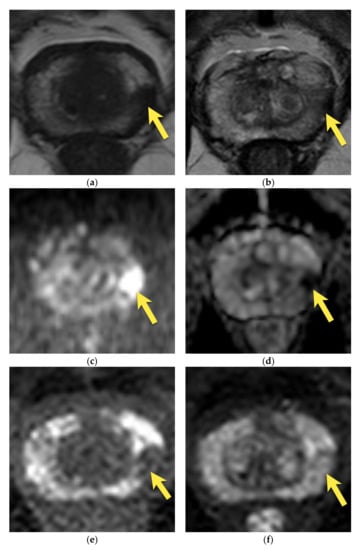

10. Prostatic Abscess